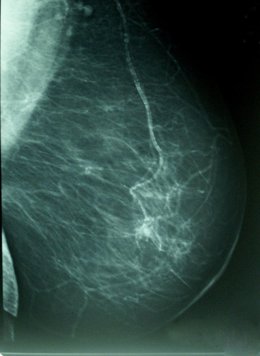

El estudio, publicado en la revista 'Breast Cancer Research and Treatment', explora la influencia de determinadas características con dicha densidad - la proporción de tejido radiológicamente blanco en la mamografía-, que es reconocido como un marcador de riesgo de cáncer de mama.

La investigación, realizada sobre una muestra 3.574 mujeres con edades comprendidas entre los 45 y los 68 años, analiza la influencia de ciertas características del nacimiento y la infancia de las mujeres con su densidad mamógrafica, un importante marcador de riesgo para cáncer de mama.